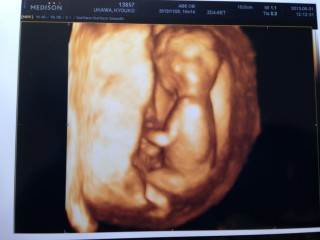

CRL81.8mm

もう赤ちゃんの形をしているのでびっくり!!後ろ姿が何とも言えないかわいさ。

心臓が4つのお部屋に分かれているのが確認出来ました。耳がパパ似?!